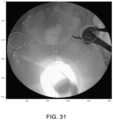

FIG.31 shows a center of rotation grid.